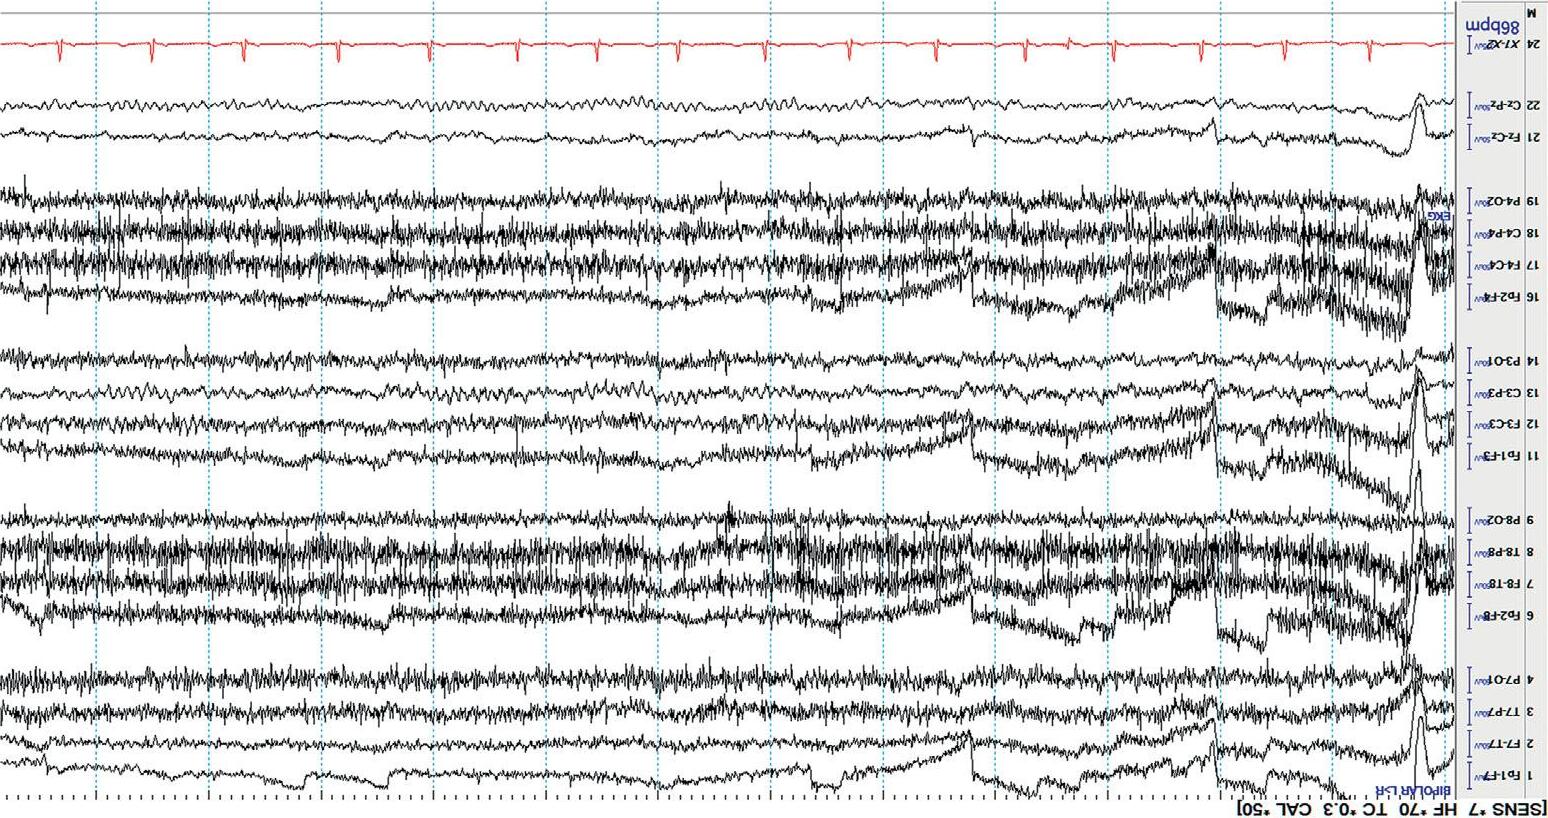

Mostdisplaysshow10or15secondsperpageofEEG. Figure1.5 showsa typicaldisplayusingthelongitudinalbipolarmontagewithexcessivemuscle artifactbefore(a)andafter(b)applicationof30Hzhighfrequencyfilter.

Figure1.5(b) ThesameEEGwithHFFsetto30Hz.